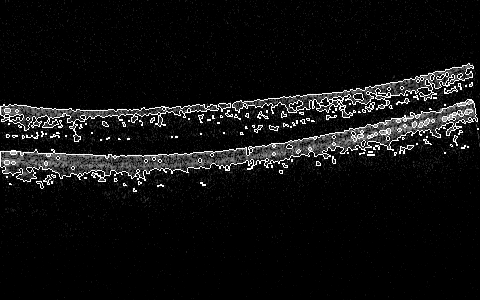

Sun et al. covered various aspects of the OCT image processing and classification using earth mover distance, SVMs, providing for detection of the nacre’s layer thickness and other works, e.g. Sun and Lei (2009, 2010). The most recent work in a 3D algorithm for segmentation (submitted) is by Sun and Zhang that explores position determination for ILM, RPE, and IS/OS in a 3D volume in an efficient and robust manner by determining intensity change on both sides of the boundary simultaneously and then smoothen the recovered surface using 3D intensity difference Sun and Zhang (2012). Some segmentation results are shown in Figure 1, and more are within the cited work.

More interesting preliminary results include global 2D (2D at the moment, per slice, but will expand the window to 3D space next) processing that includes in one algorithm some subalgorithms that do preprocessing, skeletonizing, or filling/thinning, and active-contouring of the images from the Zhang-Suen transform. There are many of the options and configurable parameters to try, but already now the outlines of the ILM, IS/OS, RPE can be seen in a very draft debug mode in Figure 7, Figure 8, Figure 5, Figure 6, Figure 9, and Figure 10.